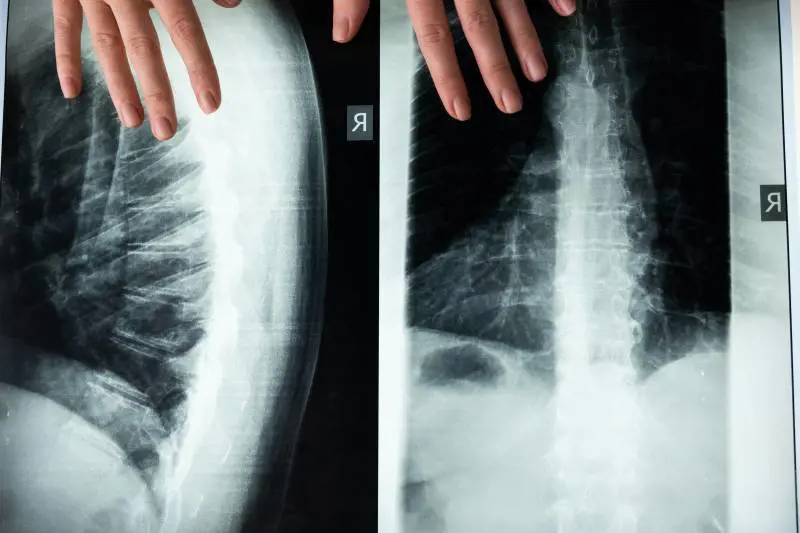

Quasi il 70% dei pazienti lamenta un dolore osseo localizzato soprattutto a livello della colonna vertebrale, del cranio, delle costole, del bacino e delle ossa lunghe. Inizialmente l’algia è intermittente, ma poi diventa cronica. Il danno osseo e le frequenti fratture sono causate dalla proliferazione della componente monoclonale nel midollo osseo che provoca osteopenia e stimolazione degli osteoclasti, le cellule responsabili della demolizione del tessuto osseo.

Il mieloma multiplo viene diagnosticato mediante test di laboratorio (esame emocromocitometrico, elettroforesi delle proteine sieriche, VES, creatinina), risonanza magnetica ed agoaspirato al fine di valutare lo stato del midollo osseo.